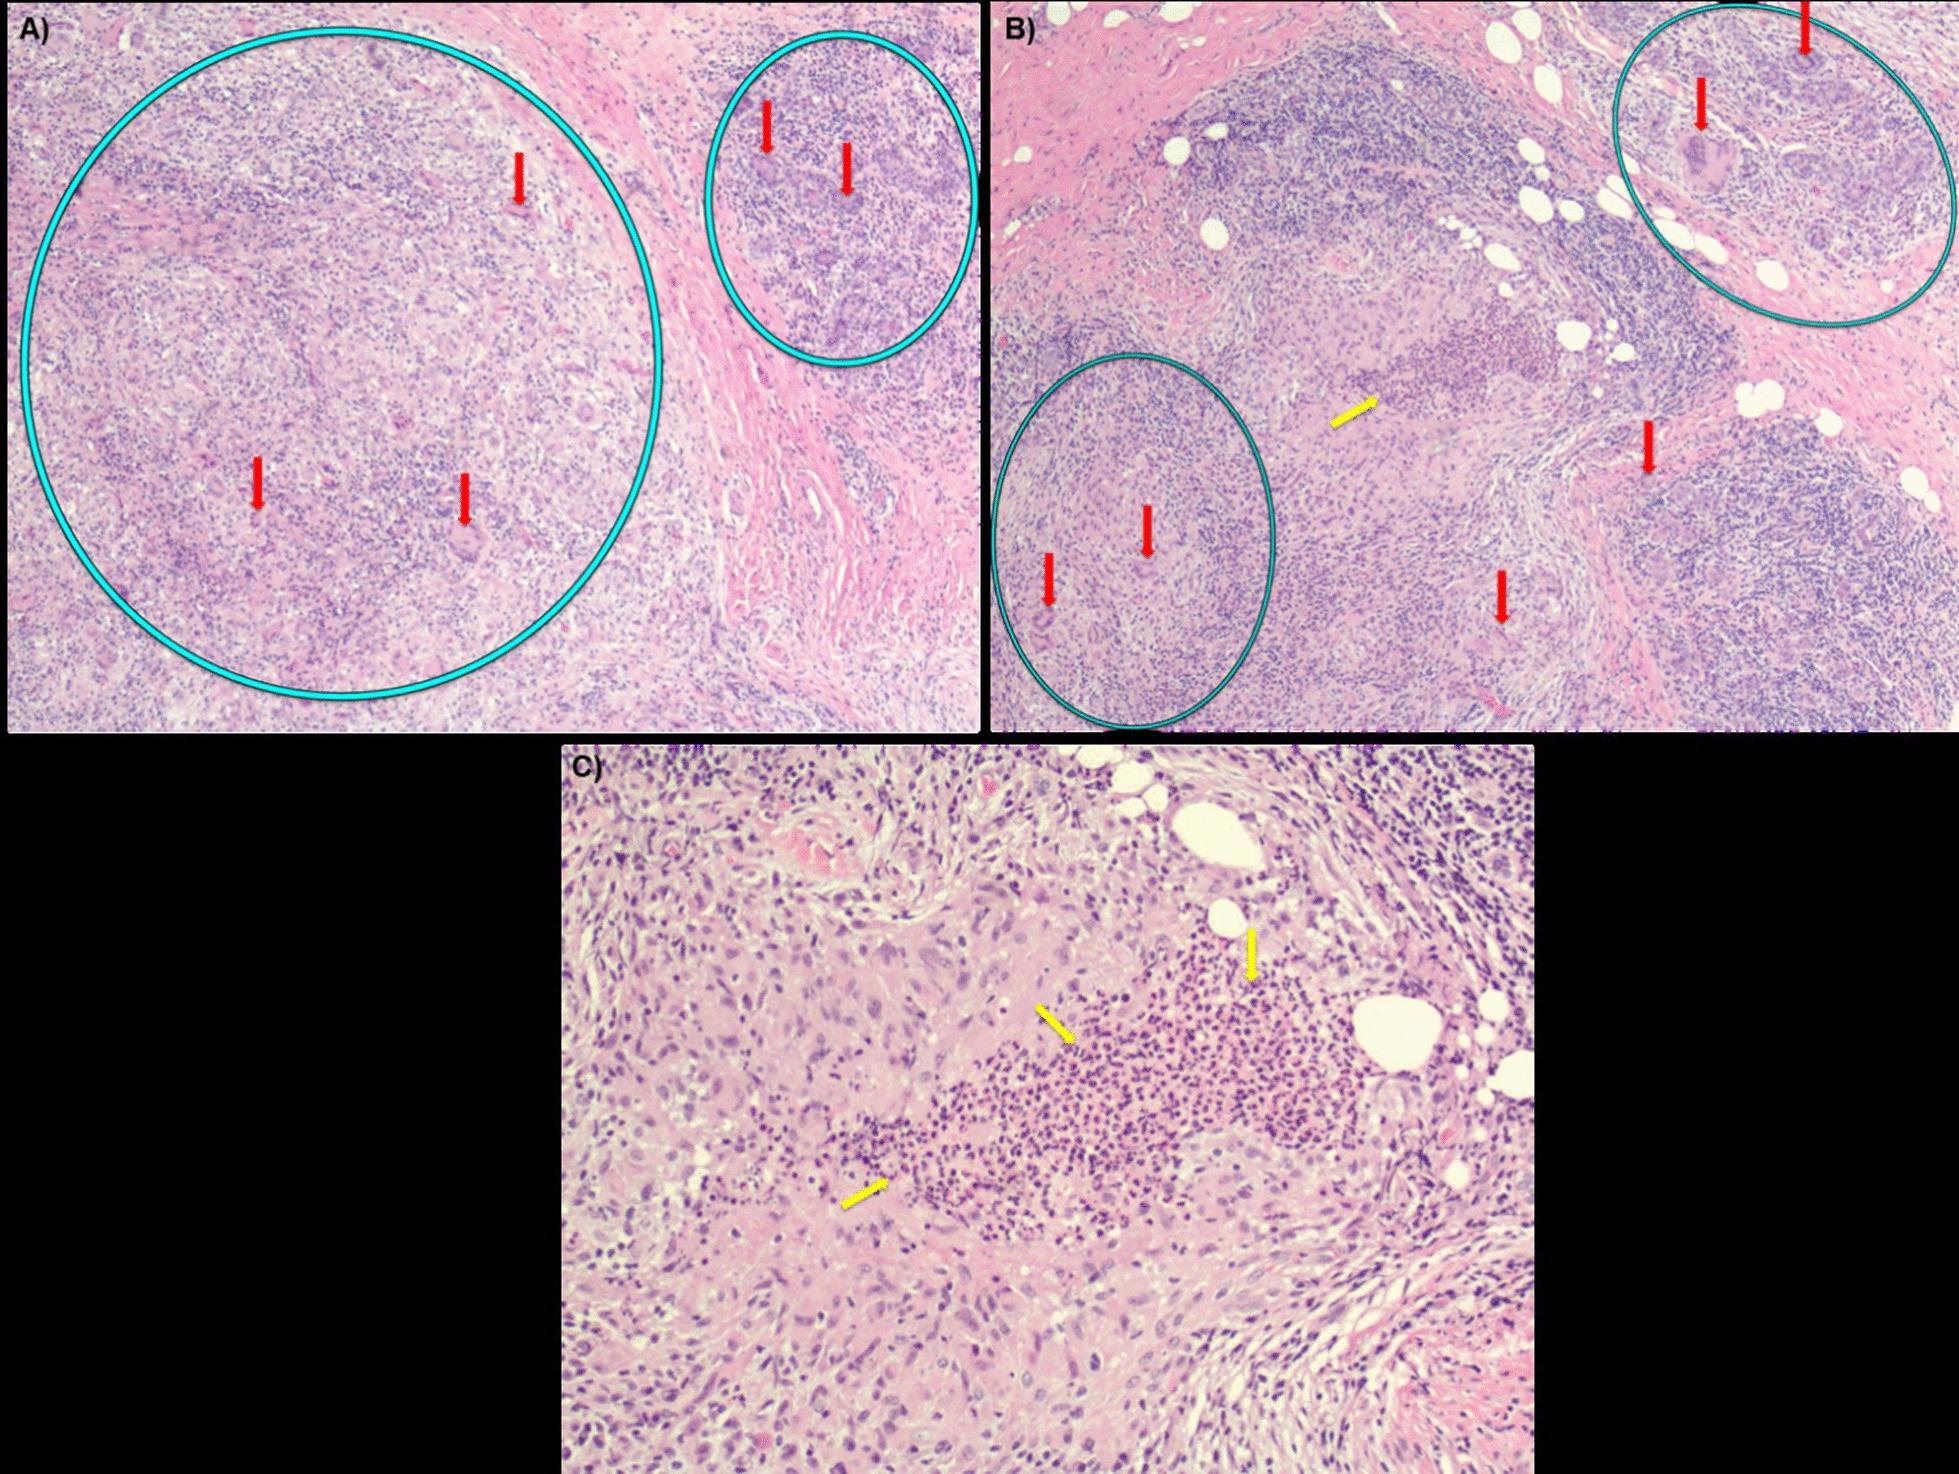

A 41-year-old G1P1 Hispanic female immigrant from Central America presented with a rare breast disease, granulomatous mastitis. A similar presentation occurred 5 years before pregnancy when she had an episode of pain and swelling in the left breast, which resolved spontaneously. She sought our services after being diagnosed with mastitis that was unsuccessfully treated. Physical examination revealed a nodular mass in the outer quadrants of the left breast without regional lymphadenopathy. Needle biopsy showed fibrohistiocytic and florid inflammatory reactions, with no evidence of invasive carcinoma. However, this result was inconsistent with the degree of abnormality revealed by the mammogram (BI-RADS grade 5), ultrasound, and physical examination. Full incisional biopsy revealed cystic neutrophilic GM. The surgical procedure, antibiotics, and corticosteroids resulted in a successful combination to secure the stable control of the symptoms and progression of this rare benign breast disease to date.

一位 41 岁的 G1P1 西班牙裔移民女性,来自中美洲,患有罕见的乳腺疾病,即肉芽肿性乳腺炎。她在怀孕前 5 年曾出现过一次左侧乳房疼痛和肿胀的类似症状,后来自行缓解。她因被诊断为乳腺炎且治疗无效而寻求我们的服务。体格检查发现左侧乳房外象限有一个结节状肿块,无区域性淋巴结肿大。针吸活检显示纤维组织细胞和明显的炎症反应,无浸润性癌的证据。然而,这一结果与乳房 X 线摄影(BI-RADS 分级 5)、超声和体格检查所显示的异常程度不一致。全切除活检显示囊状中性粒细胞性 GM。手术、抗生素和皮质类固醇的联合应用成功地控制了症状,并稳定地控制了这种罕见的良性乳腺疾病的进展。